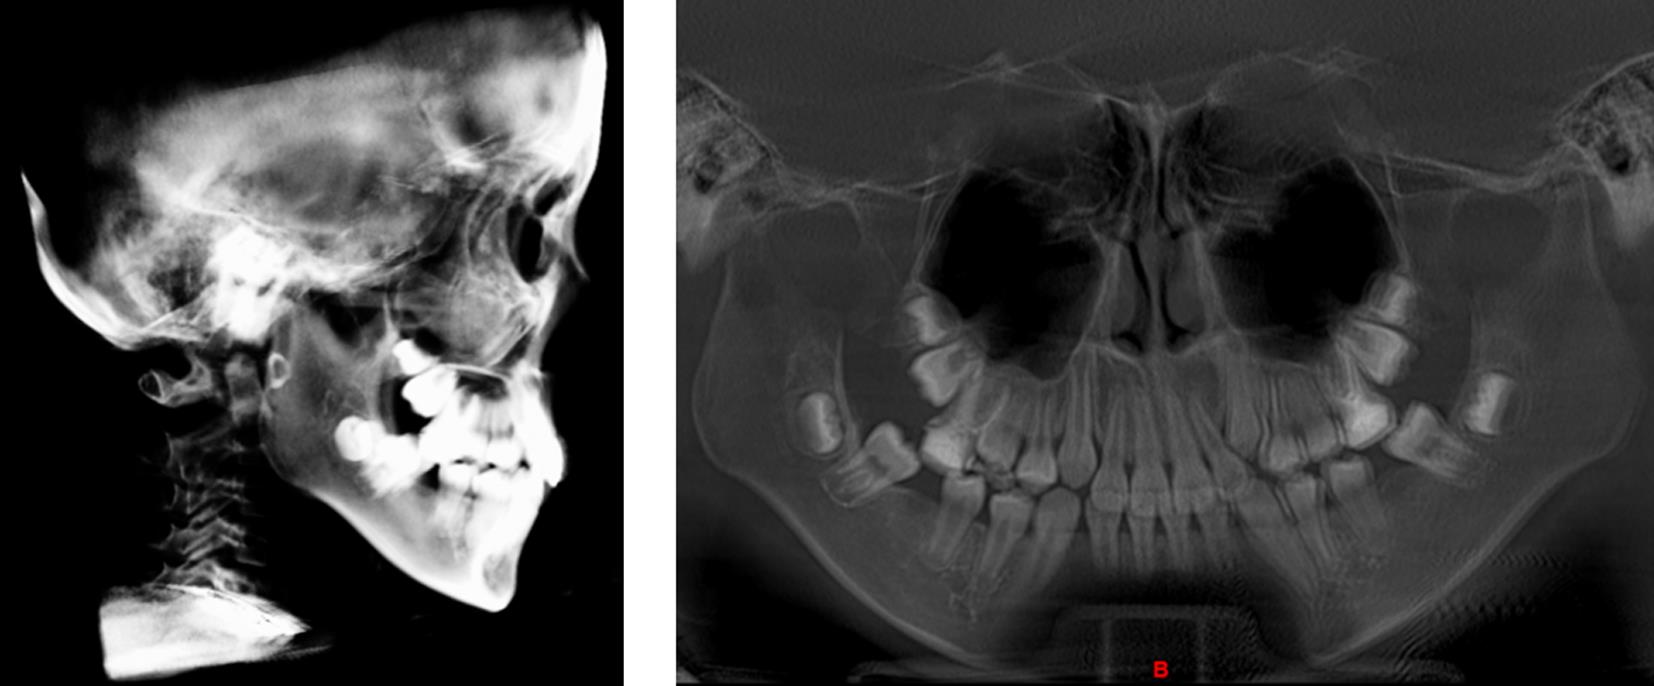

目的 探讨上颌前牵引联合个性化钛板治疗生长发育期骨性Ⅲ类错的临床效果。 方法 纳入2021年5月至2023年5月本院收治的96例生长发育期骨性Ⅲ类错

患者,采用随机数字表法分组,奇数为对照组(n = 48),偶数为观察组(n = 48),对照组予以上颌前牵引治疗,观察组予以上颌前牵引联合个性化钛板治疗,比较两组临床疗效、颌面部软组织指标(LL-EP、NLA、G-SnPg)、硬组织指标[上牙槽座角(SNA)、下牙槽座角(SNB)、上下牙槽座角(ANB)、下颌平面角度(MP-SN)、颌平面与眶耳平面(FH)角度(MP-FH)、上颌骨位置(A-OLP)、下颌骨位置(Pg-OLP)、Y轴角度(Y轴角)]、舌骨位置、牙性指标[H-X、H-Y、H-MP、H-FH]及不良反应发生情况。 结果 治疗后,观察组治疗总有效率较对照组高(P < 0.05);观察组LL-EP较对照组小(P < 0.05);观察组SNA、ANB、MP-SN、MP-FH、A-OLP及Y轴角均较对照组大(P < 0.05);观察组H-X、H-Y较对照组大(P < 0.05);观察组U1-NA较对照组大,覆

较对照组短(P < 0.05);两组不良反应发生情况无显著差异(P > 0.05)。 结论 上颌前牵引联合个性化钛板治疗可显著提升骨性Ⅲ类错

患者的临床疗效,改善软硬组织结构、舌骨位置及牙性指标,且安全性良好。